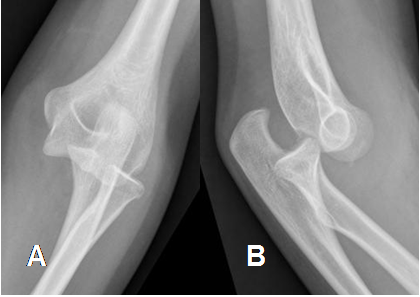

Fig 33 B. Luxación posterior del codo.

A: Rx AP y B: Rx lateral, que muestran luxación de las articulaciones ulnohumeral y radioulnar proximal.